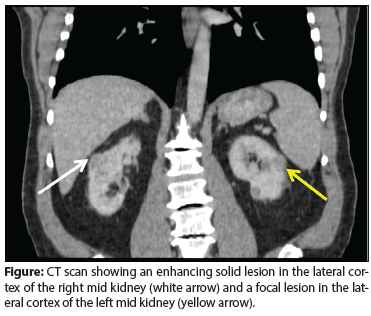

A 71-year-old woman presented with back pain and was incidentally found to have a left upper pole renal mass. She underwent left open partial nephrectomy; the pathology results revealed a 2.2-cm clear-cell renal cell carcinoma (RCC) with negative margins and a Fuhrman nuclear grade of 2.